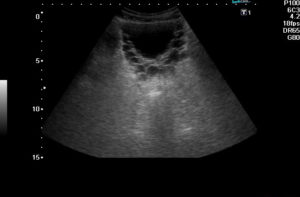

На эхо-картине пациента с острым циститом видны скопления клеток – эпителия, эритроцитов и лейкоцитов, которые в результатах исследования описываются термином «осадок». Если пациент лежит во время проведения УЗИ, то осадок локализуется около задней стенки пузыря. При вставании пациента осадок сместится к передней стенке.

При хронической форме патологии или при прогрессировании острого цистита результаты исследования покажут, что у органа неровный контур и стенки утолщены. Наличие кровяных сгустков в полости пузыря показывается на эхо-картине.

- При остром процессе сонография показывает признаки повышенной эхогенности, что свидетельствует о наличии воспалительных реакций. Осадок в моче пузырной полости выглядит в виде различных клеток и кристаллов солей. На начальном этапе развития цистита структура стенок органа остается ровной. Прогрессирование процесса вызывает развитие их ассиметричной формы.

- Хронический процесс при УЗИ отображается утолщением стенок мочевого пузыря и наличием осадочных хлопьев. При затяжном, хроническом течении процесса диагностируются наличие кровяных сгустков, прикрепленных к внутренним стенкам органа. На стадии процесса разжижения геморрагических сгустков их свертывание создает видимость неровных границ МП.

Если воспалительный процесс отсутствует, то орган мочеиспускания будет иметь округлую форму, ровные и четкие стенки, выраженные границы, утолщения, деформации, изменения в структурах отсутствуют. У здорового человека толщина слизистой стенки составляет около 5 мм. При выполнении УЗИ с допплерографией, показатель остаточной мочи не превышает 50 мл.